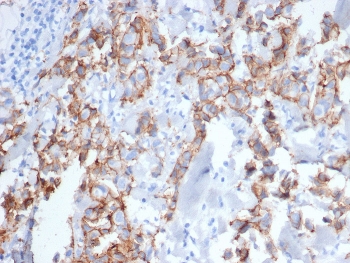

IHC staining of FFPE human breast carcinoma tissue stained with ErbB2 antibody (clone ERBB2/6637) at 2ug/ml. HIER: boil tissue sections in pH 9 10mM Tris with 1mM EDTA for 20 min and allow to cool before testing.